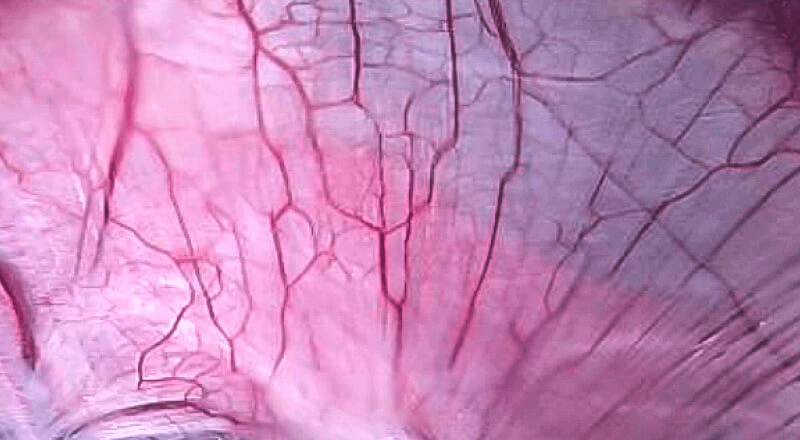

VIST光电复合染色成像技术

是一种基于血红蛋白对不同波长光吸收系数不同的原理而设计的智能染色成像系统,兼有电子染色和光学染色功能,能够凸显粘膜血管结构,有助于病灶部位识别和诊断,为临床医生术中判断提供参考信息。

• 400 500 600 700(nm)

血管对比度分布光谱曲线

• VIST光谱